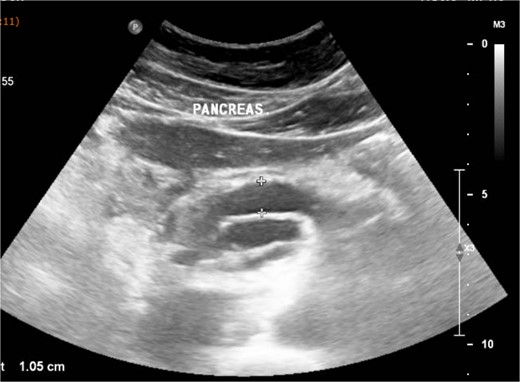

An abdominal ultrasound (Fig. 1), a computed tomography (Fig. 2) and a magnetic resonance cholangiopancreatography (MRCP) resonance showed diffuse dilation of the main pancreatic duct the duct of Santorini and the secondary ducts. Stones inside the main pancreatic duct in the head region, measuring approximately 1.1 cm. Reduction in the thickness of the pancreatic parenchyma, associated with small calcifications in between (Fig. 2).

Abdominal ultrasound shows a diffuse dilation of the main pancreatic duct.